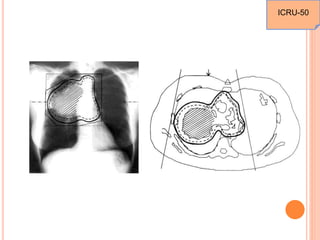

DESCRIBED VOLUMES

 Gross target volume

 Clinical target volume

 Planning target volume

 Organs at risk

 Treated volume

 Irradiated volume

ICRU-50

PLANNING TARGET VOLUME (PTV)

 The PTV is a geometrical concept, and it is defined to

select appropriate beam sizes and beam arrangements,

taking into consideration the net effect of all the possible

geometrical varaitions and inaccuracies in order to

ensure that the prescribed dose is actually absorbed in

the CTV.

 AFFECTED BY : size and shape of the GTV & CTV, the

effects of internal motions of organs and the tumour as well as

the treatment technique (beam orientation and patient fixation,

daily setup errors) used.

 The PTV can be considered as a 3-D envelope in which the

tumour and any microscopic extensions reside. The GTV and

PTV can move within this envelope, but not through it.